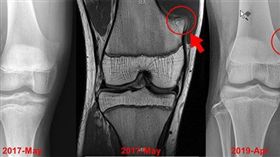

少年膝蓋痛 竟是乒乓球大骨軟骨瘤

16歲青少年2年前因膝蓋疼痛就醫,診斷為骨軟骨瘤作祟...

2019/06/04 08:14

少年打球受傷回診 醫驚:腫瘤消失了

罕見!花蓮一名16歲少年,在2年前膝蓋被診斷有「骨軟...

2019/05/28 18:06